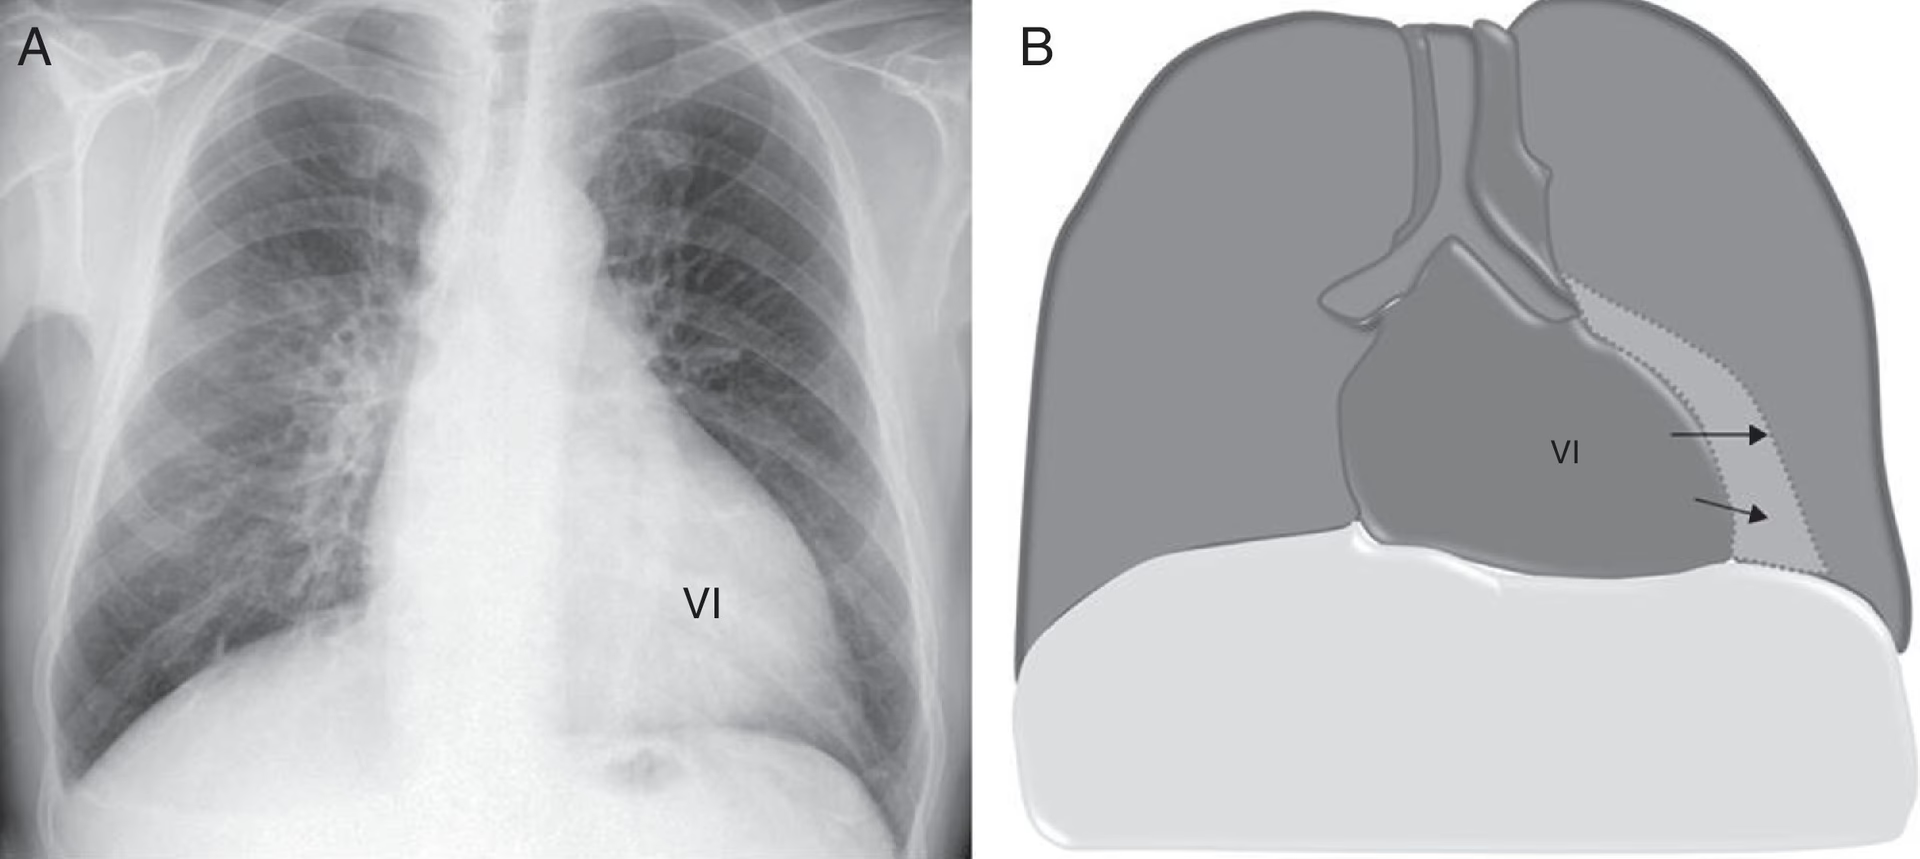

El Índice Cardiotorácico, comúnmente abreviado como ICT, es una relación métrica utilizada en la radiología para evaluar de forma cuantitativa el tamaño del corazón en comparación con el diámetro interno de la caja torácica. Se obtiene a partir de una radiografía de tórax posteroanterior (PA), que es una proyección estándar donde el paciente se encuentra de pie, con el pecho apoyado sobre el detector de rayos X y la fuente de radiación detrás de su espalda. Esta proyección es crucial porque minimiza la magnificación del corazón, proporcionando una representación más precisa de su tamaño real.

El cálculo del Índice Cardiotorácico se realiza de manera sistemática, siguiendo una serie de pasos que garantizan la mayor precisión posible. Para ello, es indispensable contar con una radiografía de tórax en proyección posteroanterior (PA) de buena calidad.

2. Medición del Diámetro Transversal Máximo del Corazón (C)

Para medir el diámetro transversal máximo del corazón, se traza una línea vertical imaginaria a través del centro de la columna vertebral. Luego, se identifican los puntos más laterales del contorno cardíaco en ambos lados (derecho e izquierdo). Se mide la distancia desde la línea central hasta el punto más lateral derecho (a) y la distancia desde la línea central hasta el punto más lateral izquierdo (b). El diámetro cardíaco (C) es la suma de estas dos distancias: C = a + b. Es fundamental ser meticuloso en esta medición, ya que pequeños errores pueden alterar significativamente el resultado final del ICT.

3. Medición del Diámetro Transversal Máximo de la Caja Torácica (T)

El diámetro transversal máximo de la caja torácica se mide en el mismo nivel que el diafragma, en su punto más ancho, de borde interno a borde interno de las costillas. Es crucial medir el diámetro interno de la caja torácica, evitando incluir la pared torácica o el tejido blando externo. Esta medida (T) representa la anchura máxima de la cavidad torácica, y es el denominador en la fórmula del ICT.

4. La Fórmula del ICT

Una vez obtenidas ambas mediciones, el cálculo del Índice Cardiotorácico es una simple división: ICT = C / T.

Donde:

- C es el diámetro transversal máximo del corazón.

- T es el diámetro transversal máximo de la caja torácica.

El resultado es un valor decimal que, como veremos, se interpreta en relación con un umbral de normalidad.